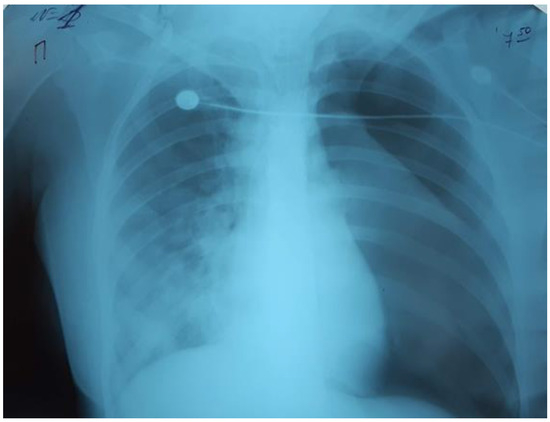

There was a further progression of RF and hypoxemia (PaO2/FiO2 117) on the background of NIV CPAP/PSV in the child, as well as the deterioration of the neurological status of the patient on the Glasgow scale (the decrease in the GCS score from 14 to 12). The control chest X-rays (performed in 24 hours) revealed a deterioration of the radiological imaging (Figure 2).

Figure 2.

The increase of the intensity of opacities on the right side, the appearance of new bilateral infiltrates.